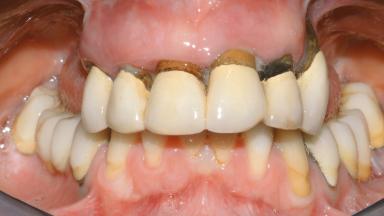

Conventional Loading of Eight Implants in the Maxilla and Final Restoration with a Full-Arch Gold-Ceramic FDP

A 35-year-old Caucasian female presenting with advanced periodontal disease involving both the maxillary and the mandibular dentition was referred for evaluation. The patient, a non-smoker in good general health, requested treatment for recurrent periodontal abscesses, tooth mobility, and discomfort during chewing, as well as restoration of her missing teeth with a fixed prosthesis to improve mastication and esthetics. All residual maxillary teeth exhibited plaque deposits, deep pockets, bleeding on probing, and class III mobility and were evaluated as hopeless. All residual mandibular teeth except tooth 37 could be maintained after periodontal therapy.

Prosthesis Type FDP